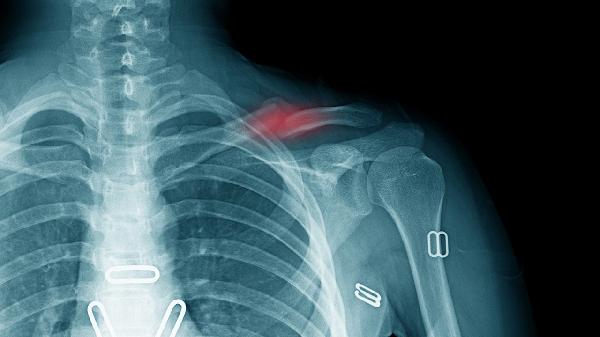

治疗骨折可使用接骨七厘片、伤科接骨片、云南白药胶囊、骨折挫伤胶囊、龙血竭片等中成药。骨折通常由外伤、骨质疏松等因素引起,建议患者在医生指导下使用药物,并配合石膏固定等治疗措施。

龙血竭片提取自龙血树树脂,具有生肌止血的作用,适用于骨折中后期愈合不良的情况。该药能刺激成骨细胞活性,但阴虚火旺者慎用,用药期间需定期复查X线观察骨痂生长情况。

骨折患者除药物治疗外,应注意加强营养摄入,多食用富含钙质的牛奶、鱼类等食物,适当补充维生素D。康复期应在医师指导下进行循序渐进的功能锻炼,避免过早负重。定期复查X线片观察骨折对位及愈合情况,若出现患肢麻木、剧烈疼痛等异常症状需立即就医。保持良好作息,戒烟限酒,有助于骨折愈合。